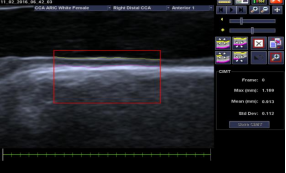

syngo®Arterial Health Package(AHP)动脉健康评估: AHP 为临床提供测量 CIMT,具有高敏感性、非侵入性等优点,测得 CIMT 的诸多参数,并联合患者的其他生理指标(血脂等)预估冠心病、脑卒中的风险指数。